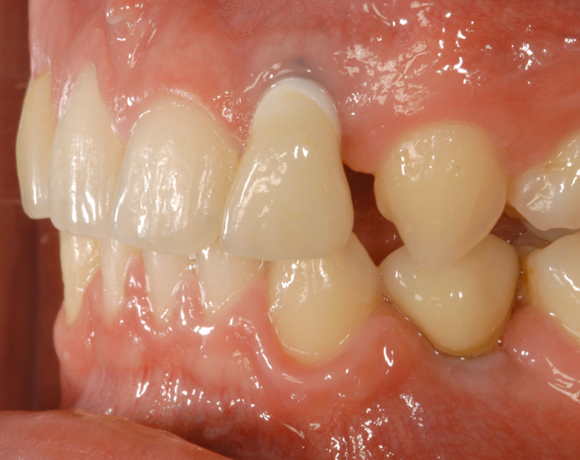

Bei diesem Patienten wurden die Nachbarzähne und das Implantat vollkeramisch versorgt.

Bei dem letzten Patientenfall lagen Nichtanlagen der Zähne 12, 24, 34, 35, 44, 45 vor. Bei Zahn 12 schimmert das Implantat durch, es war sehr wenig Knochen vorhanden, aber das Ergebnis ist seit acht Jahren konstant gut. Zahn 22 lag als Zapfenzahn vor und wurde mit einem Veneer versorgt.